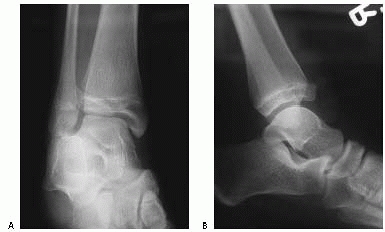

![]() |

FIGURE 26-2

Comminuted Salter-Harris type IV fracture of the distal tibia and displaced Salter-Harris type I fracture of the distal fibula produced by an inversion (shearing) mechanism in a 10-year-old girl. |

fracture of the tibia produced by a shearing (Fig. 26-2)

or crushing force might be more likely to result in growth arrest than